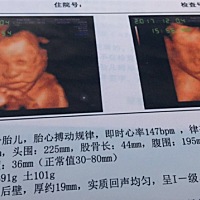

预产期倒计时开始❤️